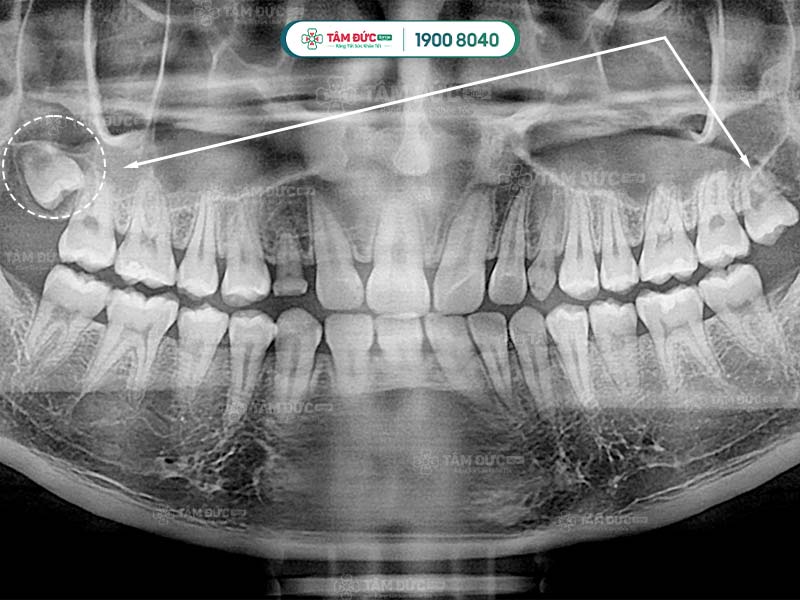

Răng khôn qua phim chụp X-Quang

Hình dạng của chân răng khôn hay còn gọi là gốc răng khôn ở mỗi người có sự khác biệt. Răng khôn có hình dáng khác với những chiếc răng còn lại, chúng hầu như có từ 2, 3 thậm chí là 4 gốc răng. Các chân này thường hợp nhất với nhau tạo thành chân lớn. Tuy nhiên, một số khác lại cuộn tròn hoặc xòe ra các hướng khác nhau.

Một số trường hợp đặc biệt, răng khôn có thể có nhiều hơn 4 chân răng. Chính vì thế, việc biết được răng khôn có mấy chân là điều cần thiết giúp bác sĩ lựa chọn giải pháp nhổ răng khôn an toàn nhất.

Đầu tiên là bước thăm khám lâm sàng để thu thập những chỉ số cần thiết như: chỉ số đông máu, số lượng tiểu cầu… Tiếp đến, Quý khách sẽ được chụp X-quang nhằm xác định răng khôn có mấy chân và hình dáng của chân răng khôn.